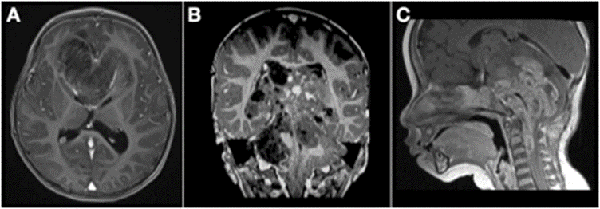

Analizando por separado los resultados de anatomías patológicas vemos que los ATRT, meduloblastomas y ependimomas tuvieron una supervivencia del 32% a los 5 años (Figuras 3 y 4) y los pacientes con tumores embrionarios, PNET, carcinomas y papilomas atípicos de plexos coroideos y pineoblastomas presentaron una mortalidad del 100% a los 5 años (Figuras 5 y 6). Por otro lado, los papilomas de plexos coroideos, lesiones más frecuentes en el grupo 1, tuvieron un 100% de supervivencia a los 10 años, al igual que los astrocitomas y gliomas de bajo grado (Figuras 7 y 8).

Figura 3: A) Paciente de 11 meses de vida, sexo masculino, que presentó macrocefalia, irritabilidad y vómitos, IRM de cerebro que mostró extensa lesión cerebelosa de aspecto nodular con intenso realce con el contraste endovenoso. B) IRM corte sagital de dicha lesión. C) IRM de cerebro postquirúrgica luego de dos cirugías de exploración y exéresis, diagnóstico de meduloblastoma desmoplásico nodular. Realizó quimioterapia y actualmente presenta un leve retraso neuromadurativo.

Figura 4: A) Paciente de 21 meses de vida, sexo masculino, que consultó por SHE y deterioro del sensorio. IRM de cerebro corte axial que evidenció lesión heterogénea en IV ventrículo y vermis con compromiso de tronco del encéfalo. B) IRM de cerebro corte sagital: ocupación de la totalidad del IV ventrículo. C) IRM de cerebro post quirúrgica, se evidenció exéresis tumoral completa, diagnóstico de ATRT de fosa posterior. Paciente falleció por progresion de enfermedad a los 6 meses.